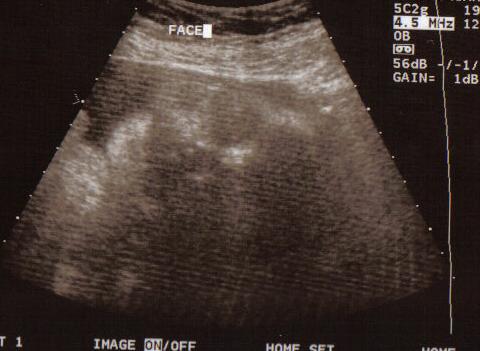

These are the last pictures of the baby until I actually get to hold him/her. We had our 37w check up and a sonogram. Everything looks great. Baby is measuring in the 50th percentile and approx. 6lbs 9oz. Image Attachment(s):

Ok...does anyone else see a face on the right looking left directly at the foot? What an imagination I have! Great pics!